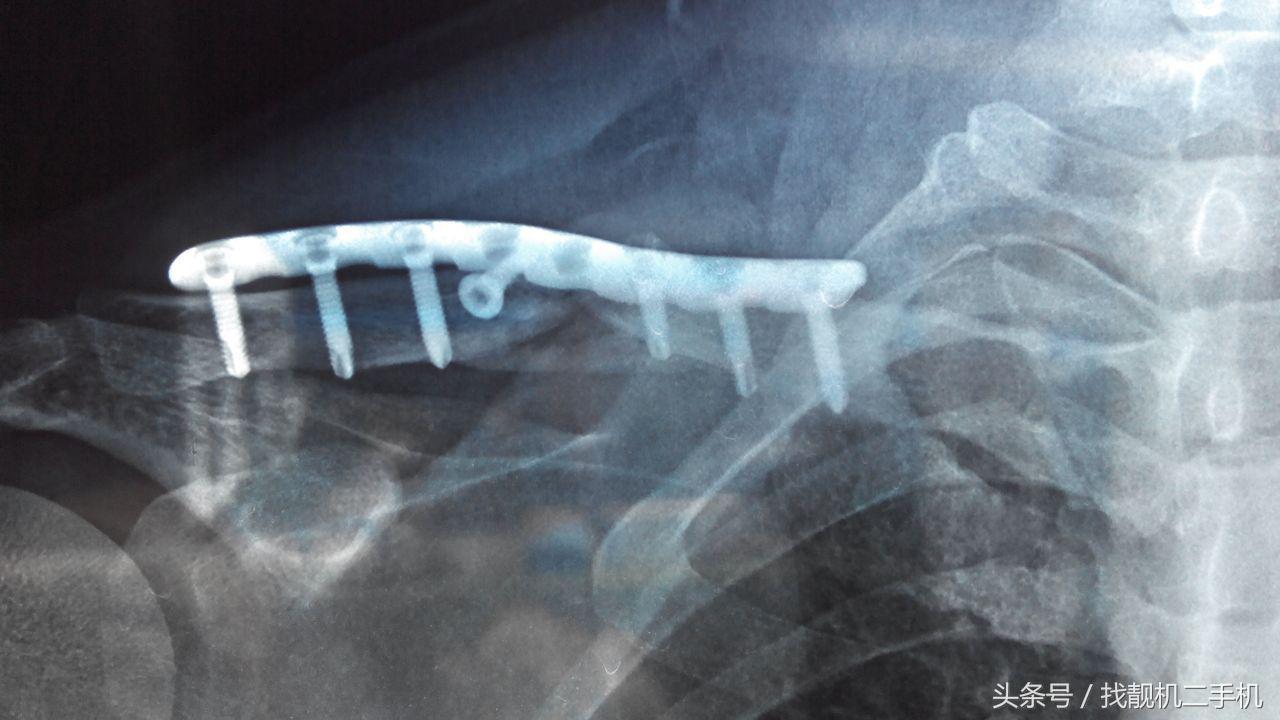

如果情况不幸,遭遇了重创,骨头碎裂比较严重, 那就得靠手术复位了。手术时,医生会将切开患处皮肤,用钢丝缝合,再根据情况选用螺丝钉、钢板、三刃钉、髓内针等内固定骨头。

更严重的,还需要将碎骨取出,用其他部位的骨头植入缺损处,最后加上石膏外固定。不过,尽管有双重保障,但粉碎性骨折一般很难恢复到原貌。